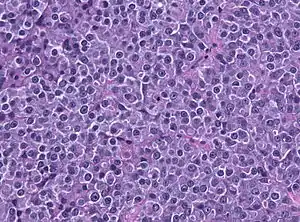

A prolactinoma is a benign tumor (adenoma) of the pituitary gland that produces a hormone called prolactin. It is the most common type of functioning pituitary tumor.[1] Symptoms of prolactinoma are due to too much prolactin in the blood (hyperprolactinemia), or those caused by pressure of the tumor on surrounding tissues. Based on size, a prolactinoma can be classified as a microprolactinoma (<10 mm diameter) or a macroprolactinoma (>10 mm diameter).